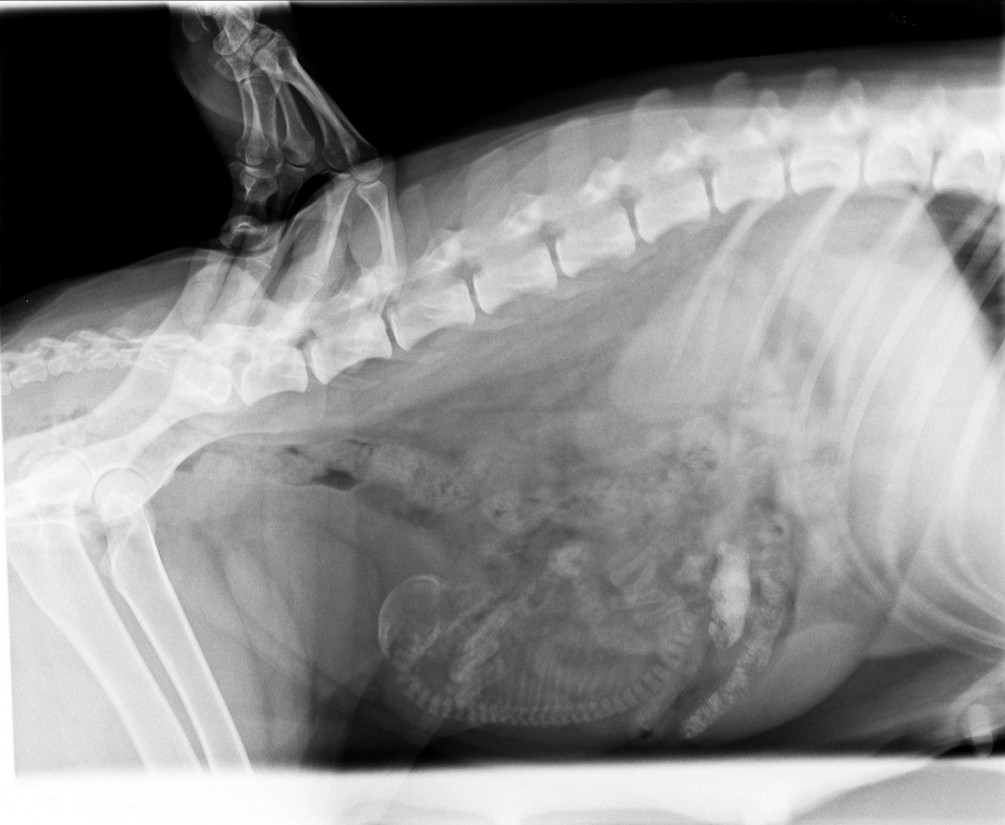

Als sich am 63. Tag immer noch nichts tat, meldeten wir uns bei der Tierärztpraxis an und machten am 64. Tag eine Röntgenaufnahme und einen Ultraschall. Im Röntgenbild zeigte sich, dass ein Welpe vorhanden war, im Ultraschall machte die Tierärztin Herztöne aus. Ansi zeigte immer noch keine Anzeichen von Wehen!

Am Vormittag gleich in die Tierklinik gefahren, der weitere Ultraschall zeigte aber, dass der Welpe tot war, keine Bewegungen, keine Herzschläge. Kaiserschnitt!!